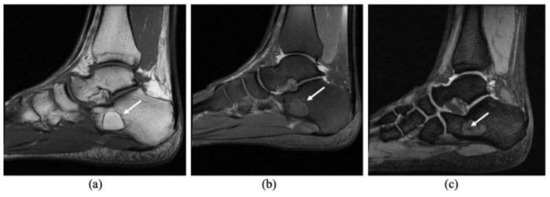

Simple bone cysts (SBCs) and intraosseous lipoma (IOL) of the calcaneus are rare tumor entities that are primarily diagnosed due to unspecific heel pain, incidental findings, or rarely due to pathological fractures. Compared to traditional open tumor resections, endoscopic resection of these benign [...] Read more.

Simple bone cysts (SBCs) and intraosseous lipoma (IOL) of the calcaneus are rare tumor entities that are primarily diagnosed due to unspecific heel pain, incidental findings, or rarely due to pathological fractures. Compared to traditional open tumor resections, endoscopic resection of these benign tumors aims to minimize surgical morbidity and maximize surgical efficiency without compromising safety. Grafting is regularly performed to reduce the risk of recurrence and stimulate osseous consolidation of the lytic lesion. As the incidence is low and treatment strategies are heterogeneous, there is no clear consensus for the treatment of simple cysts or intraosseous lipomas of the calcaneus. The objectives of this study are (a) to present medium to long-term results after endoscopic resection and grafting with allogenic cancellous bone or bioresorbable hydroxyapatite and calcium sulfate cement, and (b) to add further evidence to the discussion of whether calcaneal SBC and IOL are the same entity at different developmental stages. Between 2012 and 2019, a total of 25 benign bone tumors consisting of 17 SBCs and 8 IOLs were treated by A.T. with endoscopic resection and grafting, comprising the largest cohort to date. For grafting, 12 patients received allogenic cancellous bone (group A) and 13 patients received injectable bone substitute (group B). Pre- and postoperative imaging using plain X-rays and MRI was retrospectively analyzed with a mean follow-up time of 24.5 months to assess tumor size, osseous consolidation (modified Neer classification), and tumor recurrence. A retrospective chart analysis focusing on adverse intra- and perioperative events and other complications associated with the surgical procedure was performed using the modified Clavien–Dindo classification (CD1-3). A total of 12/13 cases with allogenic bone grafting showed a Neer Type 1 osseous healing of the tumorous lesion after endoscopic resection, whereas only 5/11 cases with injectable bone substitute showed sufficient healing (types 1 and 2). There were three recurrent cysts (Neer 4) and two persistent cysts (Neer 3) after using injectable bone substitute. Two CD1 complications were observed in group A (prolonged wound drainage, sural neuritis) and eight complications were observed in group B (6× CD1, 2× CD3). At least two IOLs diagnosed preoperatively using MRI were ultimately identified as SBCs upon histopathologic examination. Allogenic cancellous bone grafting after endoscopic resection of calcaneal SBC or IOL showed a very low rate of complications and no tumor recurrence in our series. On the other hand, depending on the material used, injectable bone substitute showed a high rate of “white-out” (excessive drainage), resulting in multiple complications such as prolonged wound healing, insufficient permanent defect filling, recurrence, and revision surgery. Over time, calcaneal SBC may transform into IOL, exhibiting distinct features of both entities simultaneously during ossoscopy and histopathological analysis. Full article